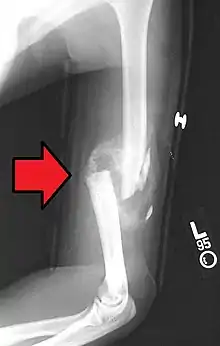

Distal humerus fractures usually occur as a result of physical trauma to the elbow region. If the elbow is bent during the trauma, then the olecranon is driven upward, producing a T- or Y-shaped fracture or displacing one of the condyles.[7]

Definitive diagnosis of humerus fractures is typically made through radiographic imaging. For proximal fractures, X-rays can be taken from a scapular anteroposterior (AP) view, which takes an image of the front of the shoulder region from an angle, a scapular Y view, which takes an image of the back of the shoulder region from an angle, and an axillar lateral view, which has the patient lie on his or her back, lift the bottom half of the arm up to the side, and have an image taken of the axilla region underneath the shoulder.[9] Fractures of the humerus shaft are usually correctly identified with radiographic images taken from the AP and lateral viewpoints.[12] Damage to the radial nerve from a shaft fracture can be identified by an inability to bend the hand backwards or by decreased sensation in the back of the hand.[5] Images of the distal region are often of poor quality due to the patient being unable to extend the elbow because of pain. If a severe distal fracture is suspected, then a computed tomography (CT) scan can provide greater detail of the fracture. Nondisplaced distal fractures may not be directly visible; they may only be visible due to fat being displaced because of internal bleeding in the elbow.[7]